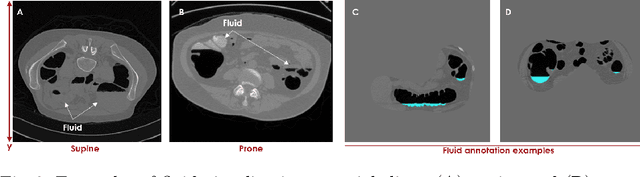

Abstract:High-resolution colon segmentation is crucial for clinical and research applications, such as digital twins and personalized medicine. However, the leading open-source abdominal segmentation tool, TotalSegmentator, struggles with accuracy for the colon, which has a complex and variable shape, requiring time-intensive labeling. Here, we present the first fully automatic high-resolution colon segmentation method. To develop it, we first created a high resolution colon dataset using a pipeline that combines region growing with interactive machine learning to efficiently and accurately label the colon on CT colonography (CTC) images. Based on the generated dataset consisting of 435 labeled CTC images we trained an nnU-Net model for fully automatic colon segmentation. Our fully automatic model achieved an average symmetric surface distance of 0.2 mm (vs. 4.0 mm from TotalSegmentator) and a 95th percentile Hausdorff distance of 1.0 mm (vs. 18 mm from TotalSegmentator). Our segmentation accuracy substantially surpasses TotalSegmentator. We share our trained model and pipeline code, providing the first and only open-source tool for high-resolution colon segmentation. Additionally, we created a large-scale dataset of publicly available high-resolution colon labels.